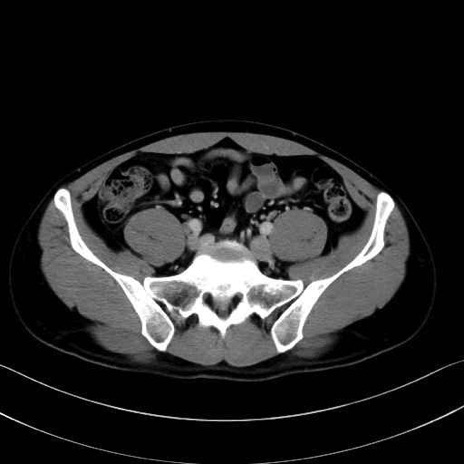

腰方形筋(quadratus lumborum muscle)のCT画像の解剖

2. 腸腰筋群と骨盤底筋

大腰筋 (Psoas major)

腸骨筋 (Iliacus)